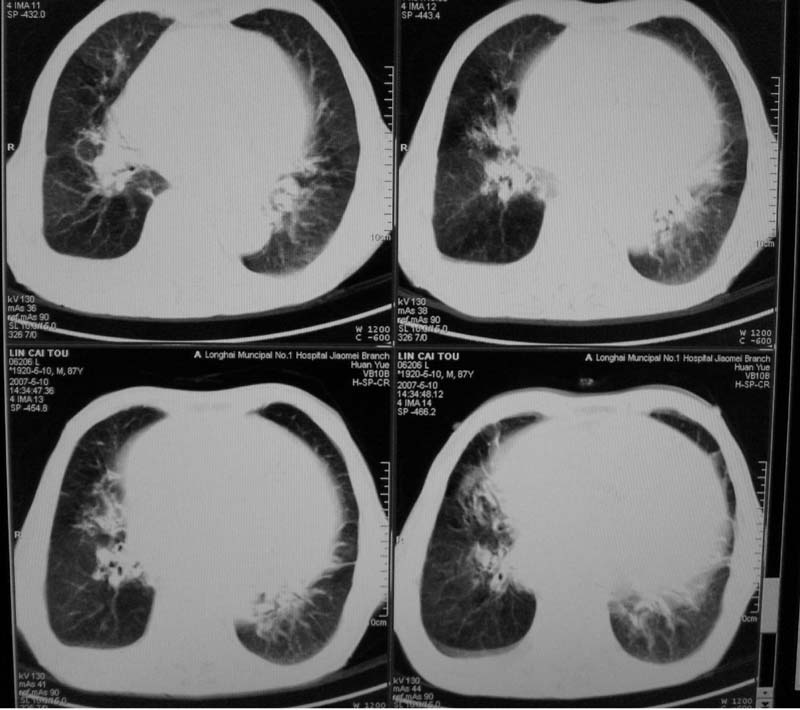

以下是引用小初学者在2007-5-12 16:26:00的发言:[br]1、心衰肺水肿两侧胸腔积液2、心包积液3、心瓣膜钙化